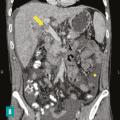

Thrombose porte et ischémie mésentérique veineuses

La thrombose de la veine porte (TVP) se caractérise par l’obstruction, le plus souvent par un thrombus, de la veine porte et/ou de ses branches portales (droite et/ou gauche). Cette obstruction peut être partielle ou complète, récente (moins de six mois) ou chronique (plus de six mois) et peut également affecter les vaisseaux…